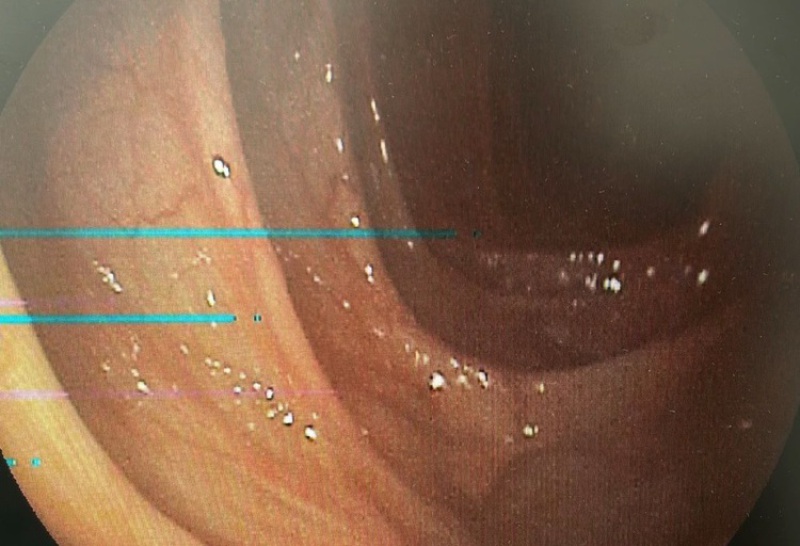

... grünes Bild auf dem Monitor.

genauste Analyse des Problems

Beim Eincheck in die Werkstatt wird Ihr Gerät genaustens

auf technische Fehler geprüft.